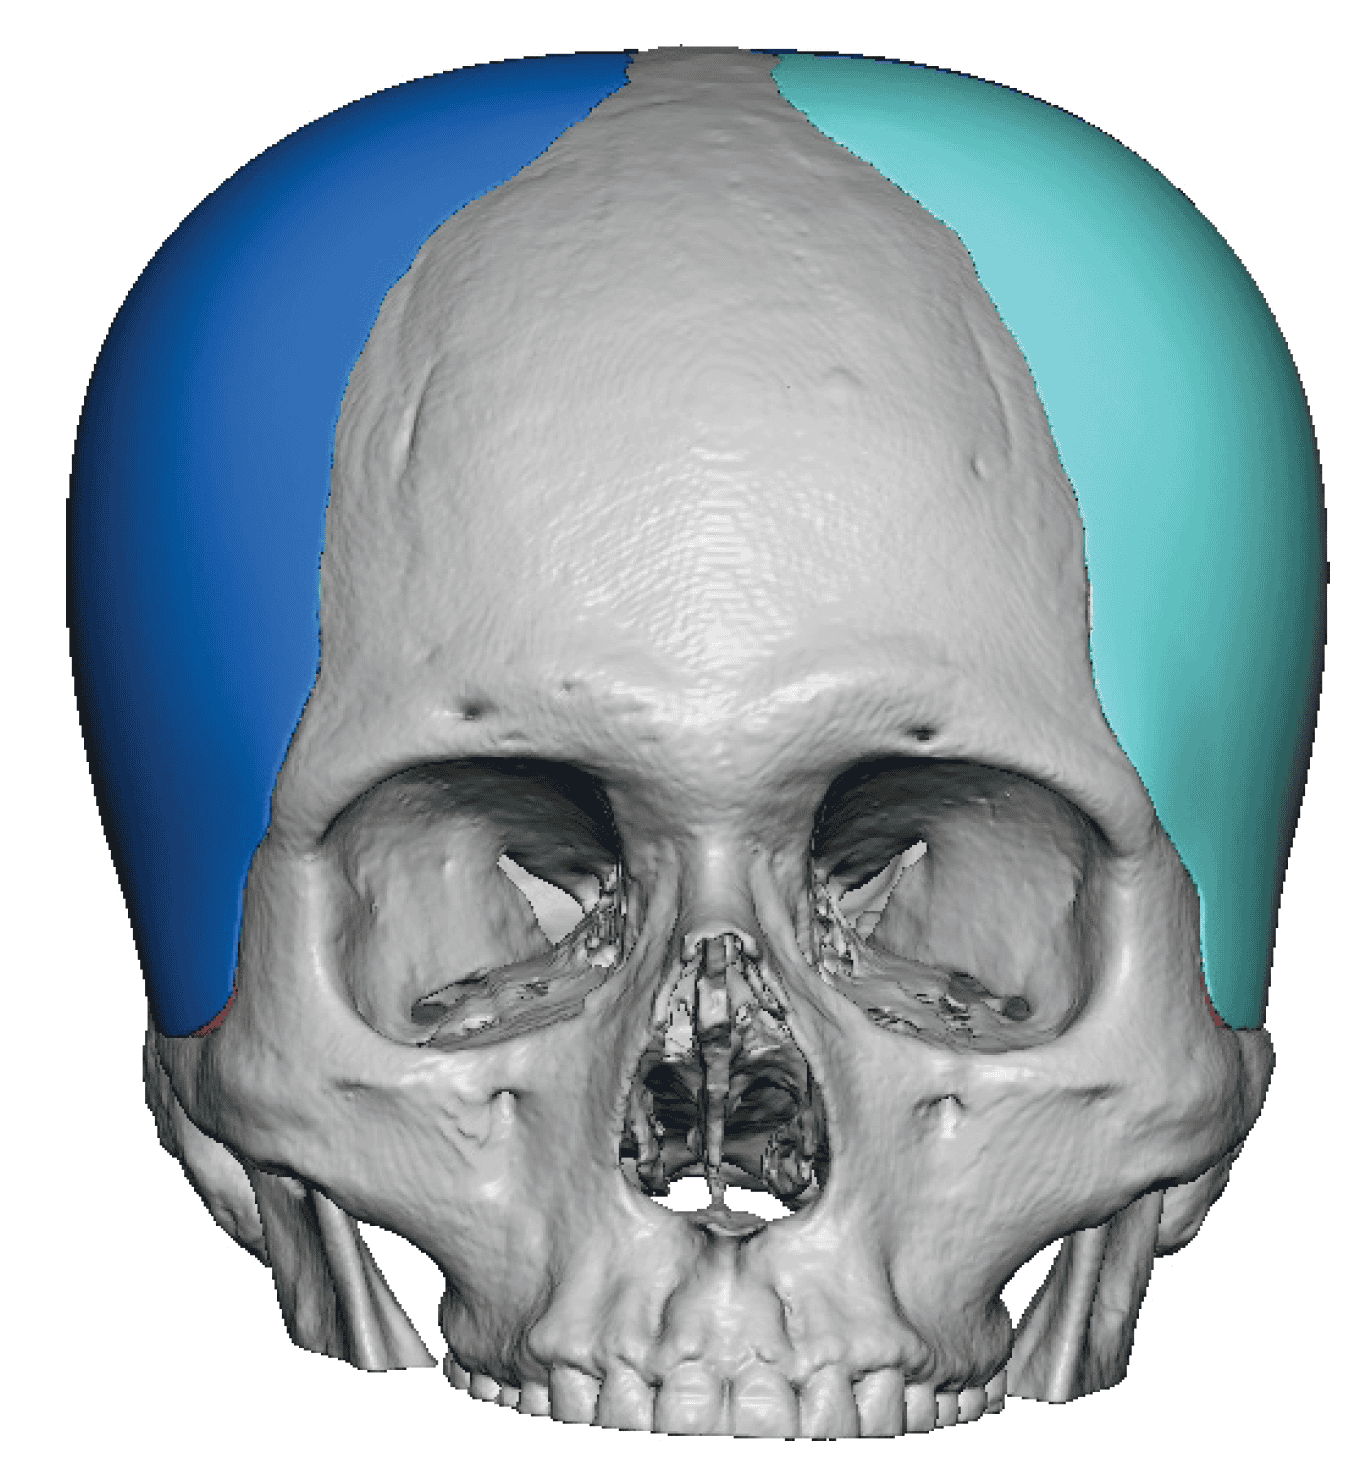

Patient 28

Desire for rounder shape to the top of the head from a congenital parasagittal deficiency skull shape.

Custom skull implant designed to fill in the parasagittal deficiencies.

Desire for rounder shape to the top of the head from a congenital parasagittal deficiency skull shape.

Custom skull implant designed to fill in the parasagittal deficiencies.